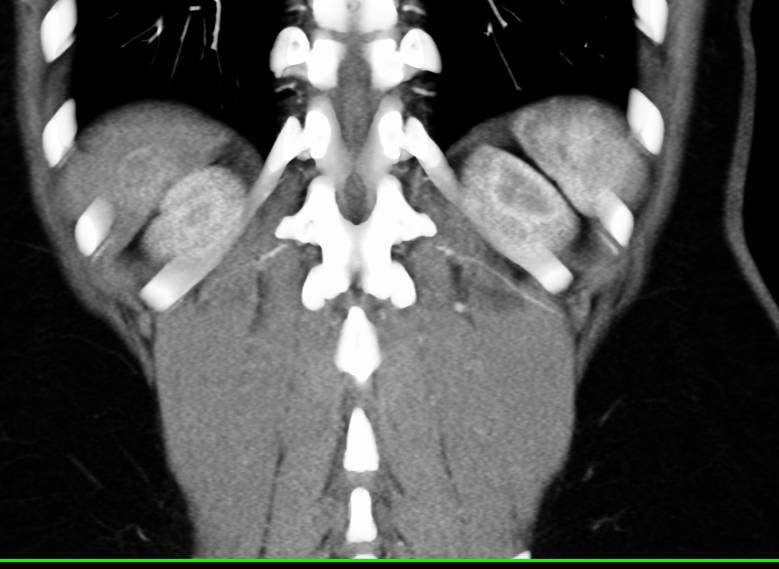

Hepatocellular Carcinoma (Hepatoma) with Neovascularity